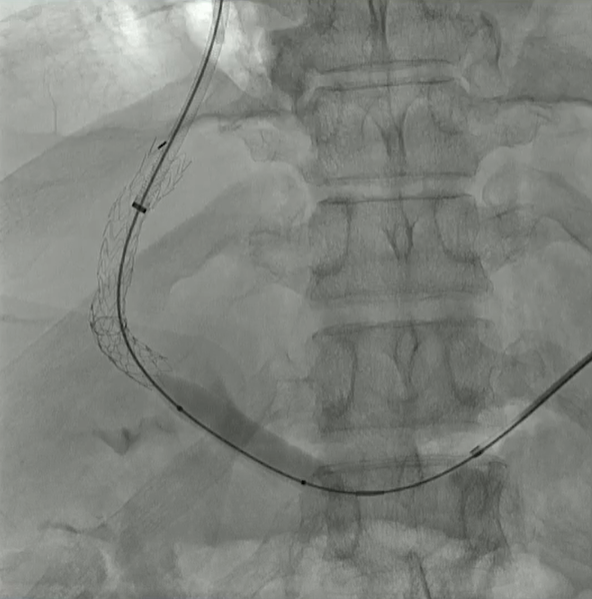

结果:术后影像学检查显示门静脉和脾静脉的血流情况有所改善,且残留血栓极少。

通过经颈静脉肝内门体分流术(TIPS)治疗慢性门静脉血栓时所涉及的技术复杂性和决策难题,尤其是在标准方法因血栓程度过重而无法实施的情况下更是如此。 采用脾经脏穿刺术治疗门静脉高压症的方法证明能够有效克服这些难题,从而成功实施了经颈静脉肝内门体分流术(TIPS)。 PVR-TIPS 作为一线治疗方案:PVR-TIPS 为慢性门静脉血栓的治疗提供了一种技术上可行的解决方案,克服了标准 TIPS 安装所面临的难题。 持久效果:该干预措施不仅恢复了门静脉的血流,而且在后续随访中还显示出持续的通畅性以及血栓的完全消散。